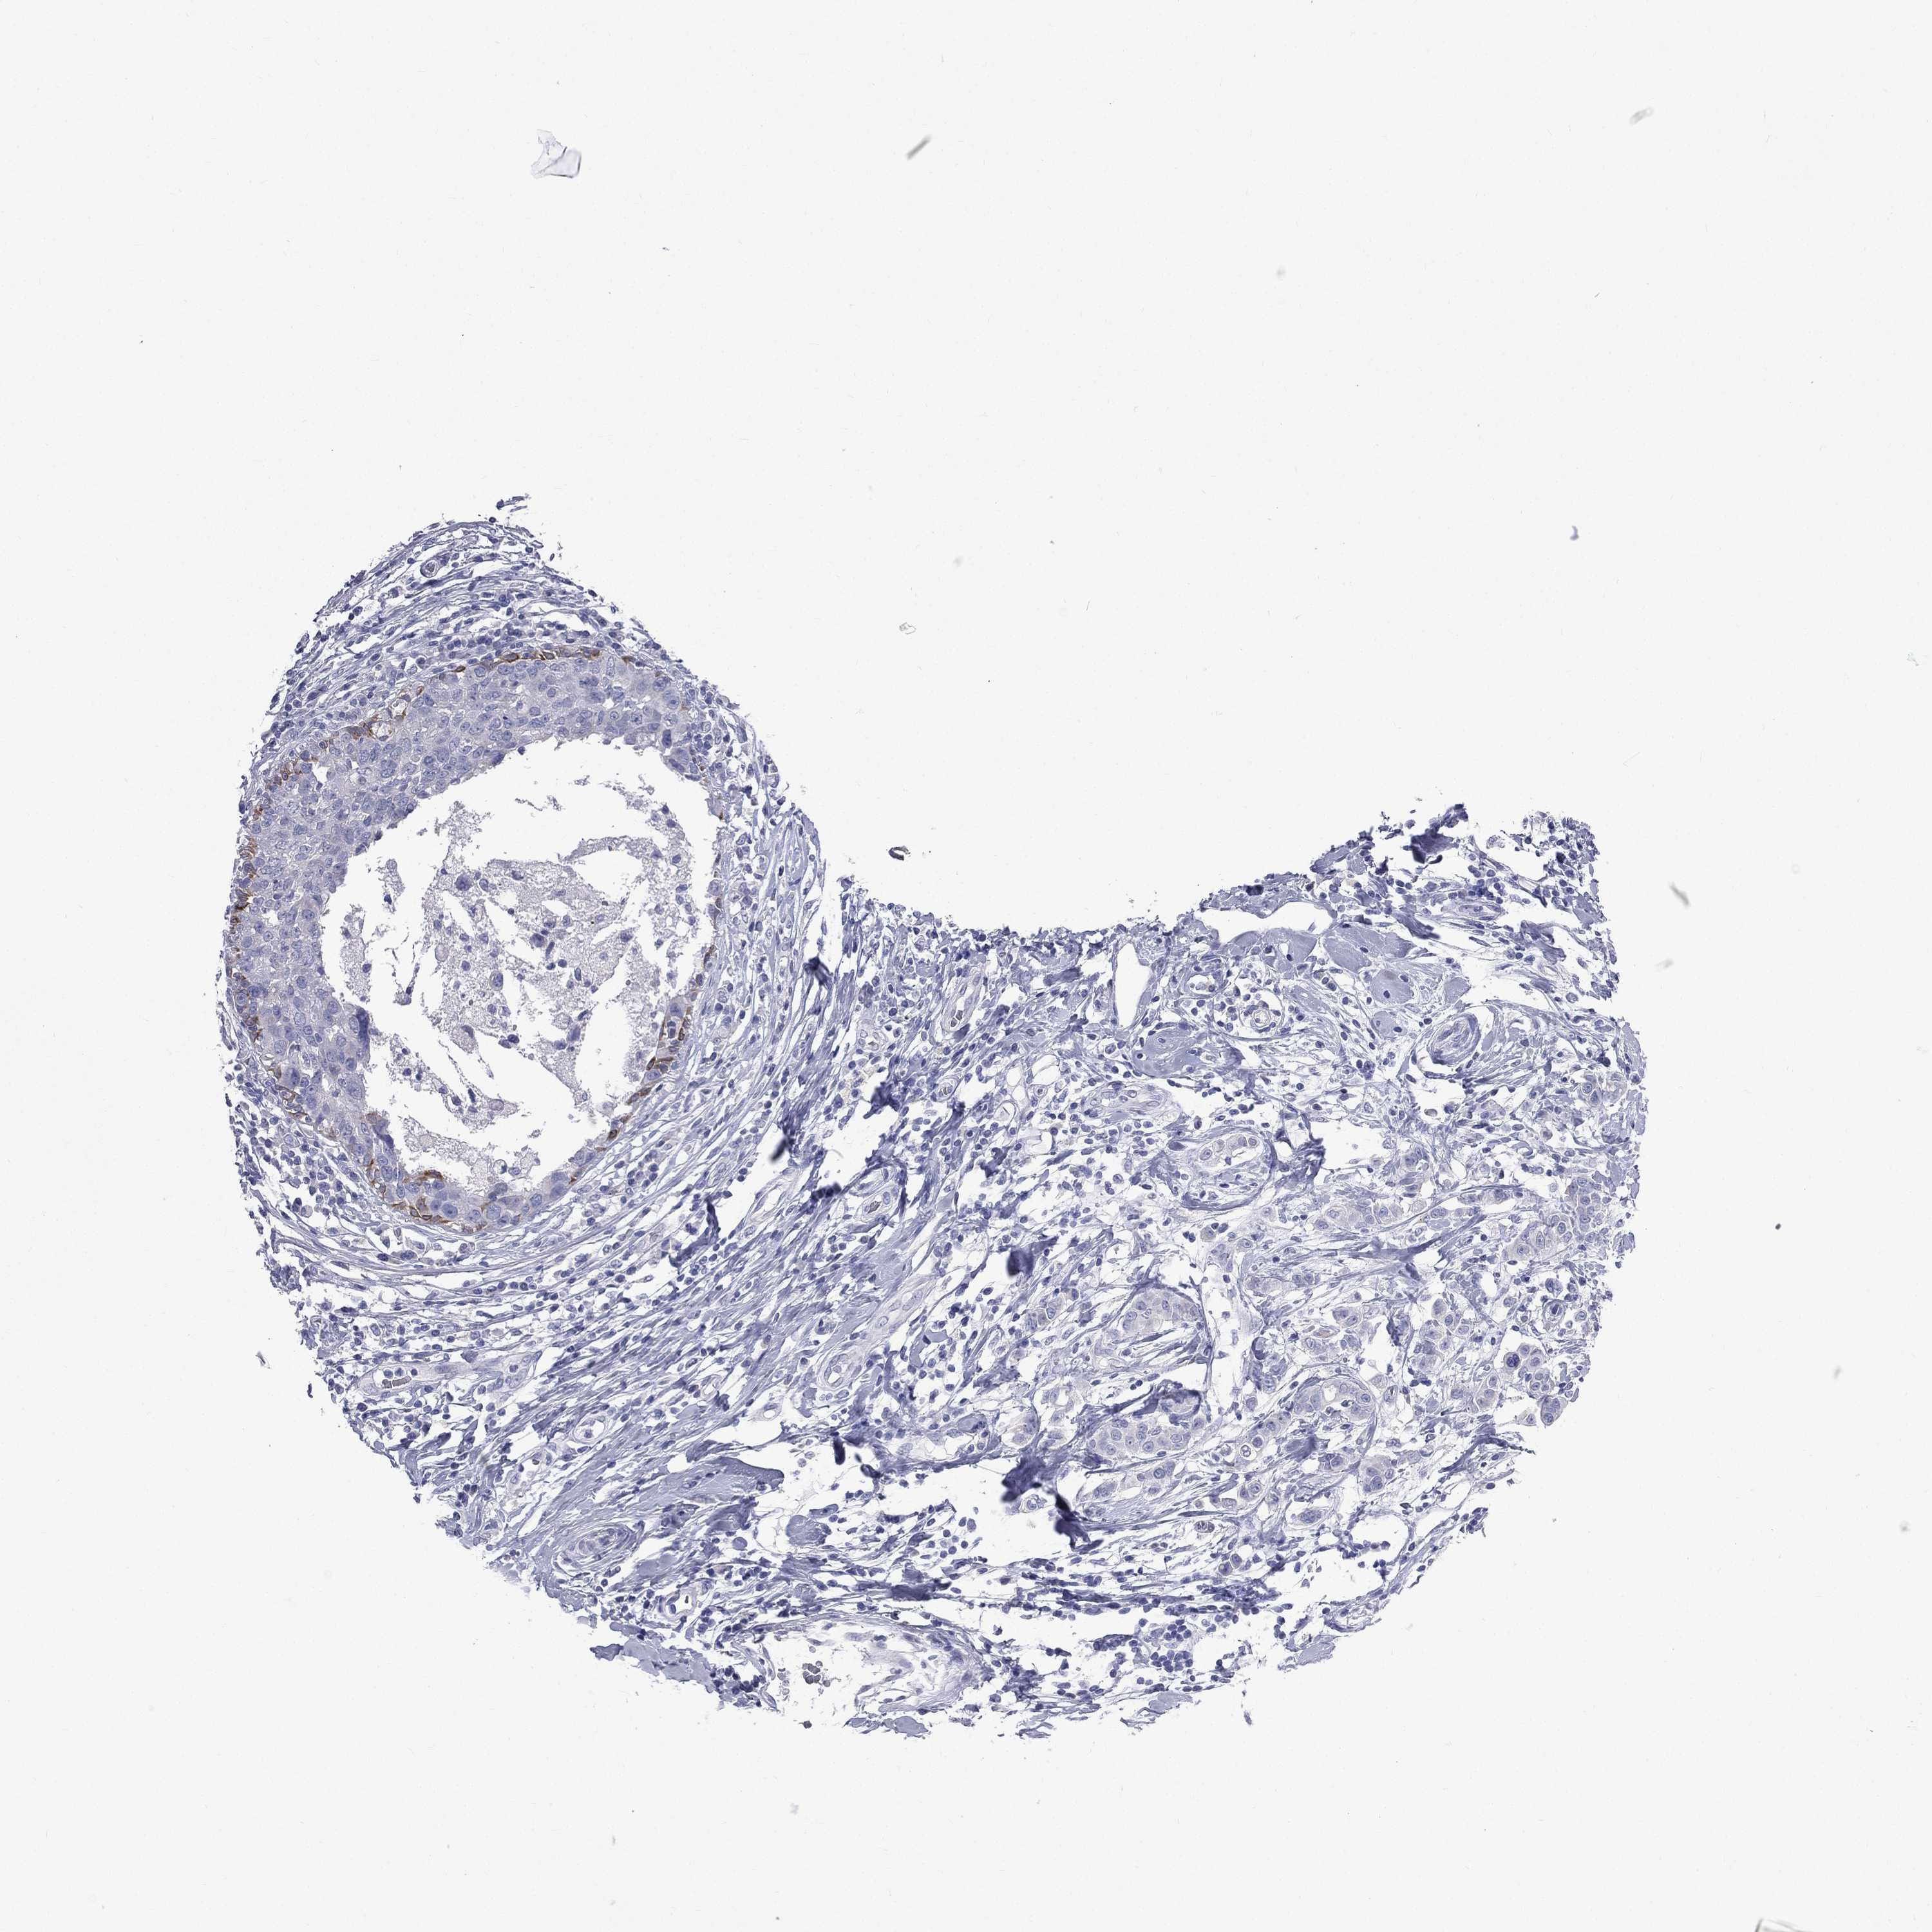

CANCER BREAST CANCER Show tissue menu

BRCA TCGA BRCA VALIDATION PROTEIN EXPRESSION

ANTIBODIES

AND

VALIDATION